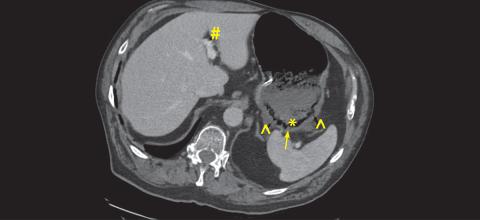

Initial CT scan on postadmission day 1 showing the presence of intramural gas, portal venous gas, hypoenhancing posterior stomach body, and gas in vasculature of stomach.

Successful nonoperative management of gastric ischemia and portal venous gas secondary to Sarcina ventriculi infection

Sarcina ventriculi is a gram-positive anaerobic bacterium with a characteristic tetrad morphology.[1,2] It is technically part of the Clostridium genus and is therefore occasionally referred to as Clostridium ventriculi... Read More